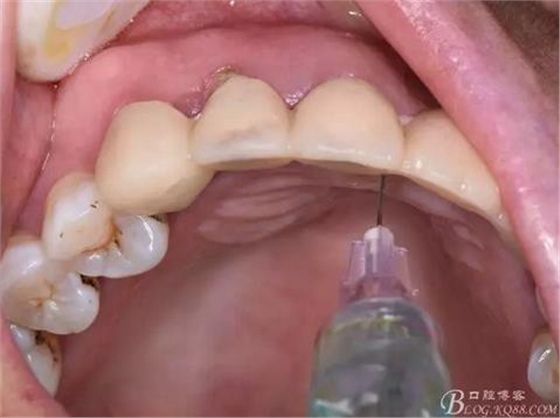

圖5.唇側(cè)局部浸潤麻醉

圖6.腭側(cè)浸潤麻醉